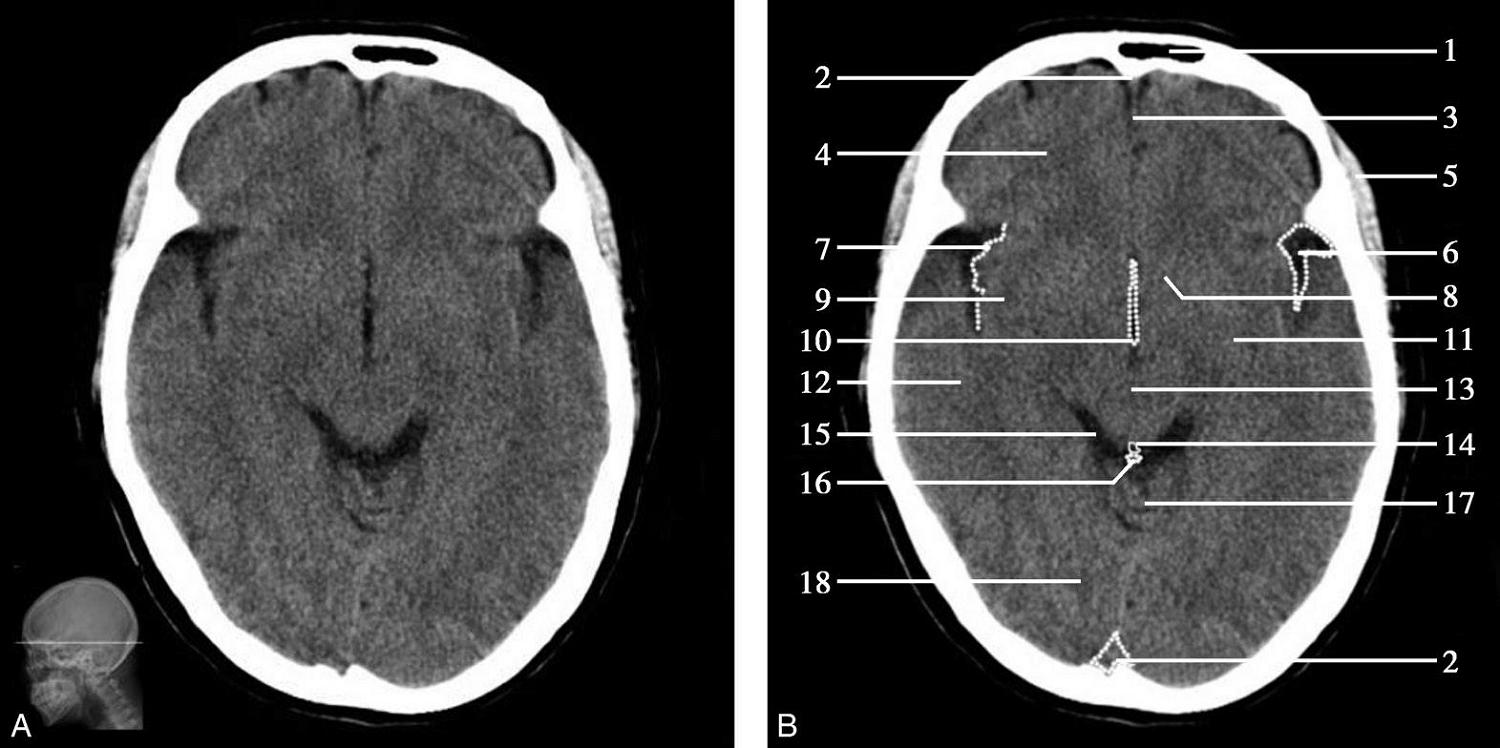

松果体、苍白球在成人期常出现钙化,属生理性钙化,一般无病理意义。需注意勿误诊为出血灶,尤其是单侧苍白球钙化时(图1-2-28)。

图1-2-28 苍白球生理性钙化

A.双侧苍白球对称性钙化,呈高密度影(箭);B.左侧苍白球钙化(箭),右侧苍白球钙化不明显